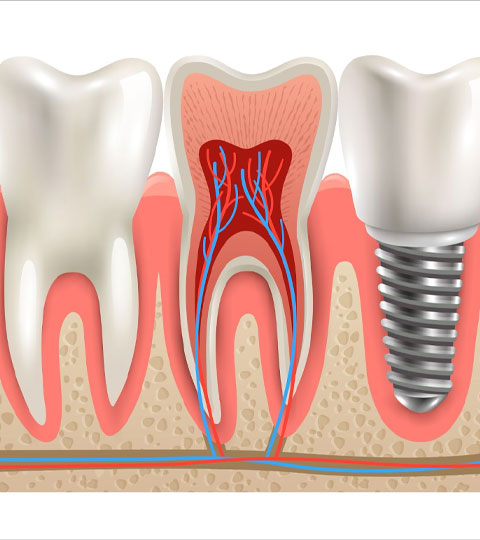

- Dental Implants in the Philippines

- Dental Implants in the Philippines